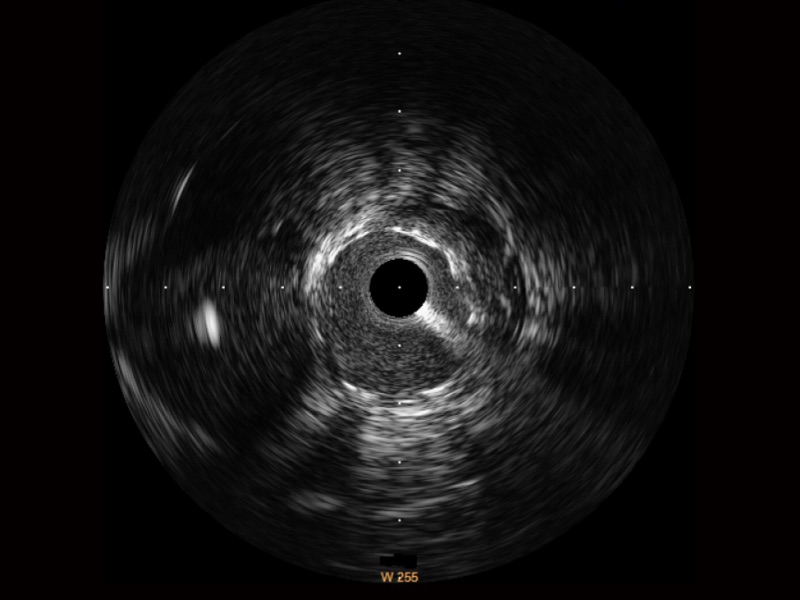

血管内超声(IVUS) 通过对病变程度、性质和累及范围的精确判断,可帮助选择治疗策略和方法,指导介入治疗过程,能够降低主要不良心血管事件,改善预后,在复杂病变介入治疗中用于指导支架置入的优势更为明显。血管内超声(IVUS)已成为精准心血管介入治疗的“金标准”。

银河优越会始终关注未满足的临床需求:超宽频成像技术同时提供高清分辨力和充足穿透深度,适应不同血管结构的治疗引导;智慧赋能,简化操作,降低临床应用难度和缩短学习曲线。